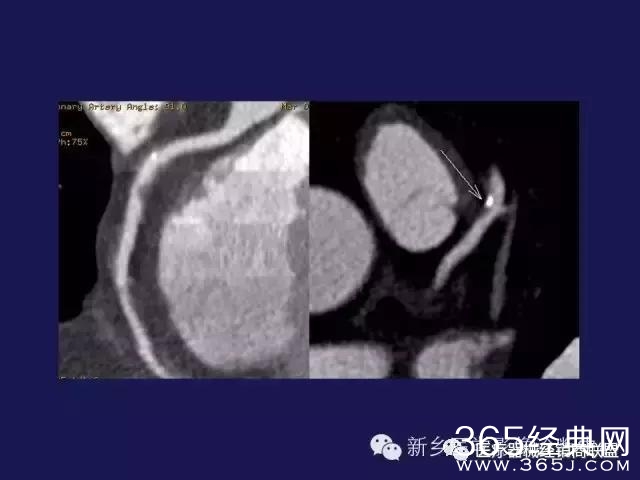

CT、MRI很难?NO,今日我们一起来学习一下如何读CT、MRI!

内行看门道: